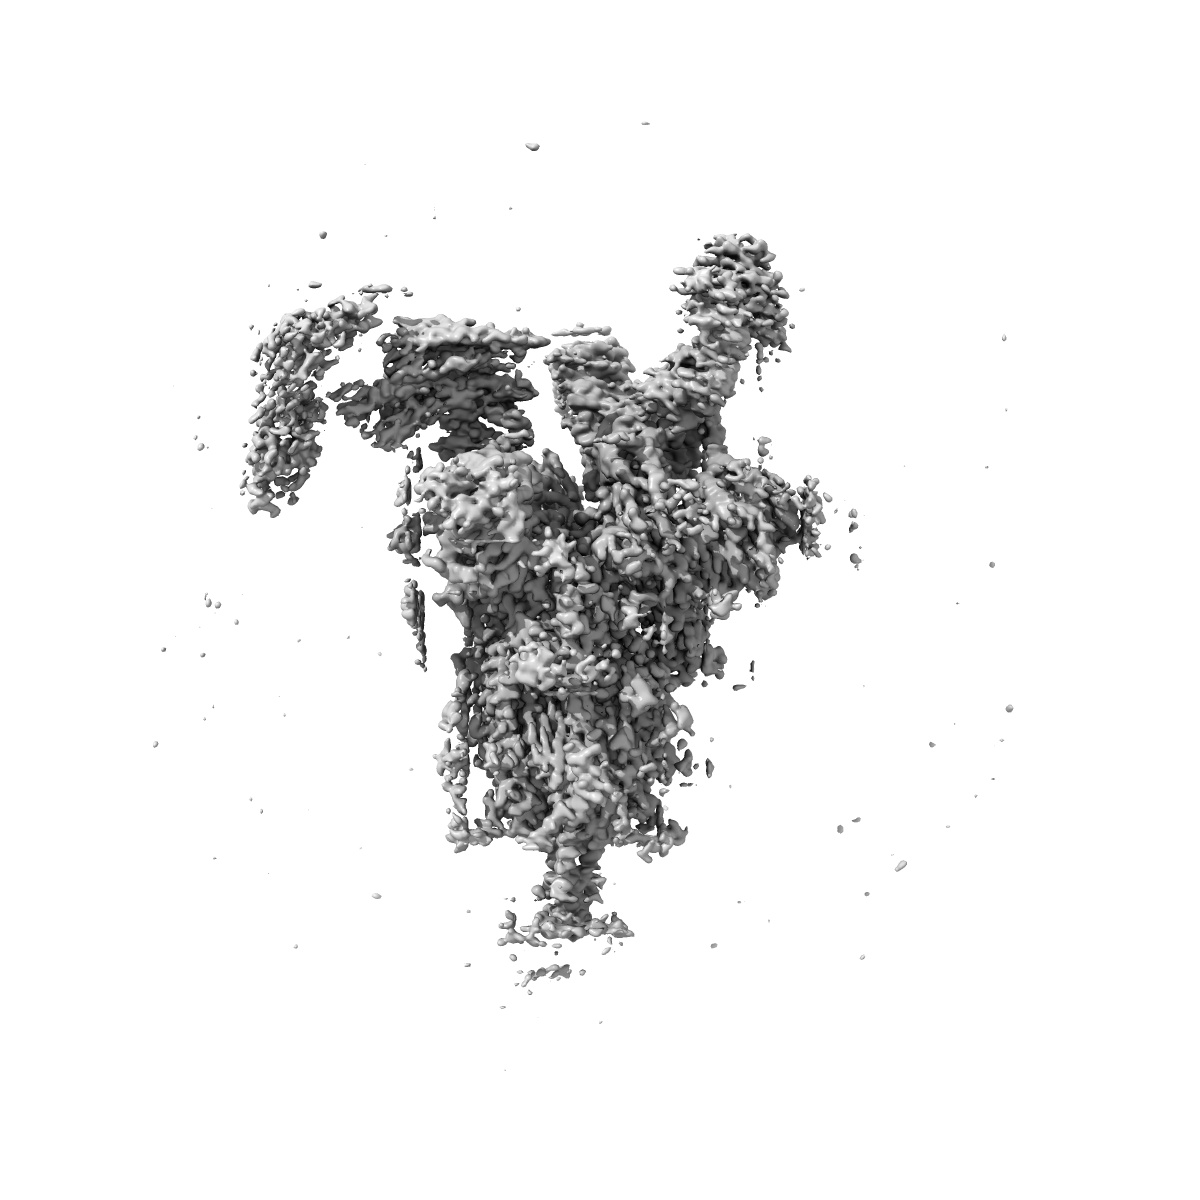

SARS-CoV-2 Omicron Variant S Trimer complexed with three JMB2002 Fab

Single-particle2.92 Å

Sample: SARS-CoV-2 Omicron Variant S Trimer complexed with JMB2002 Fab

Structures of the Omicron spike trimer with ACE2 and an anti-Omicron antibody.

(2022) Science , 375 , 1048 - 1053